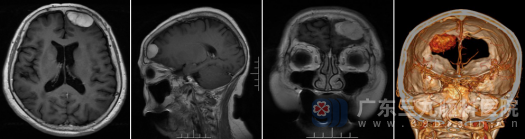

入院后,神经外十科团队为王阿婆安排了详尽的术前评估。头颅MR增强扫描显示:左侧额部存在一大小约34.5×18.1×25.1mm的占位性病变。影像学上,该病变呈现ASL高灌注特征,这意味着肿瘤血供极其丰富,术中稍有不慎极易引发大出血。初步诊断为“脑膜瘤可能性大”,但不排除孤立性纤维性肿瘤。